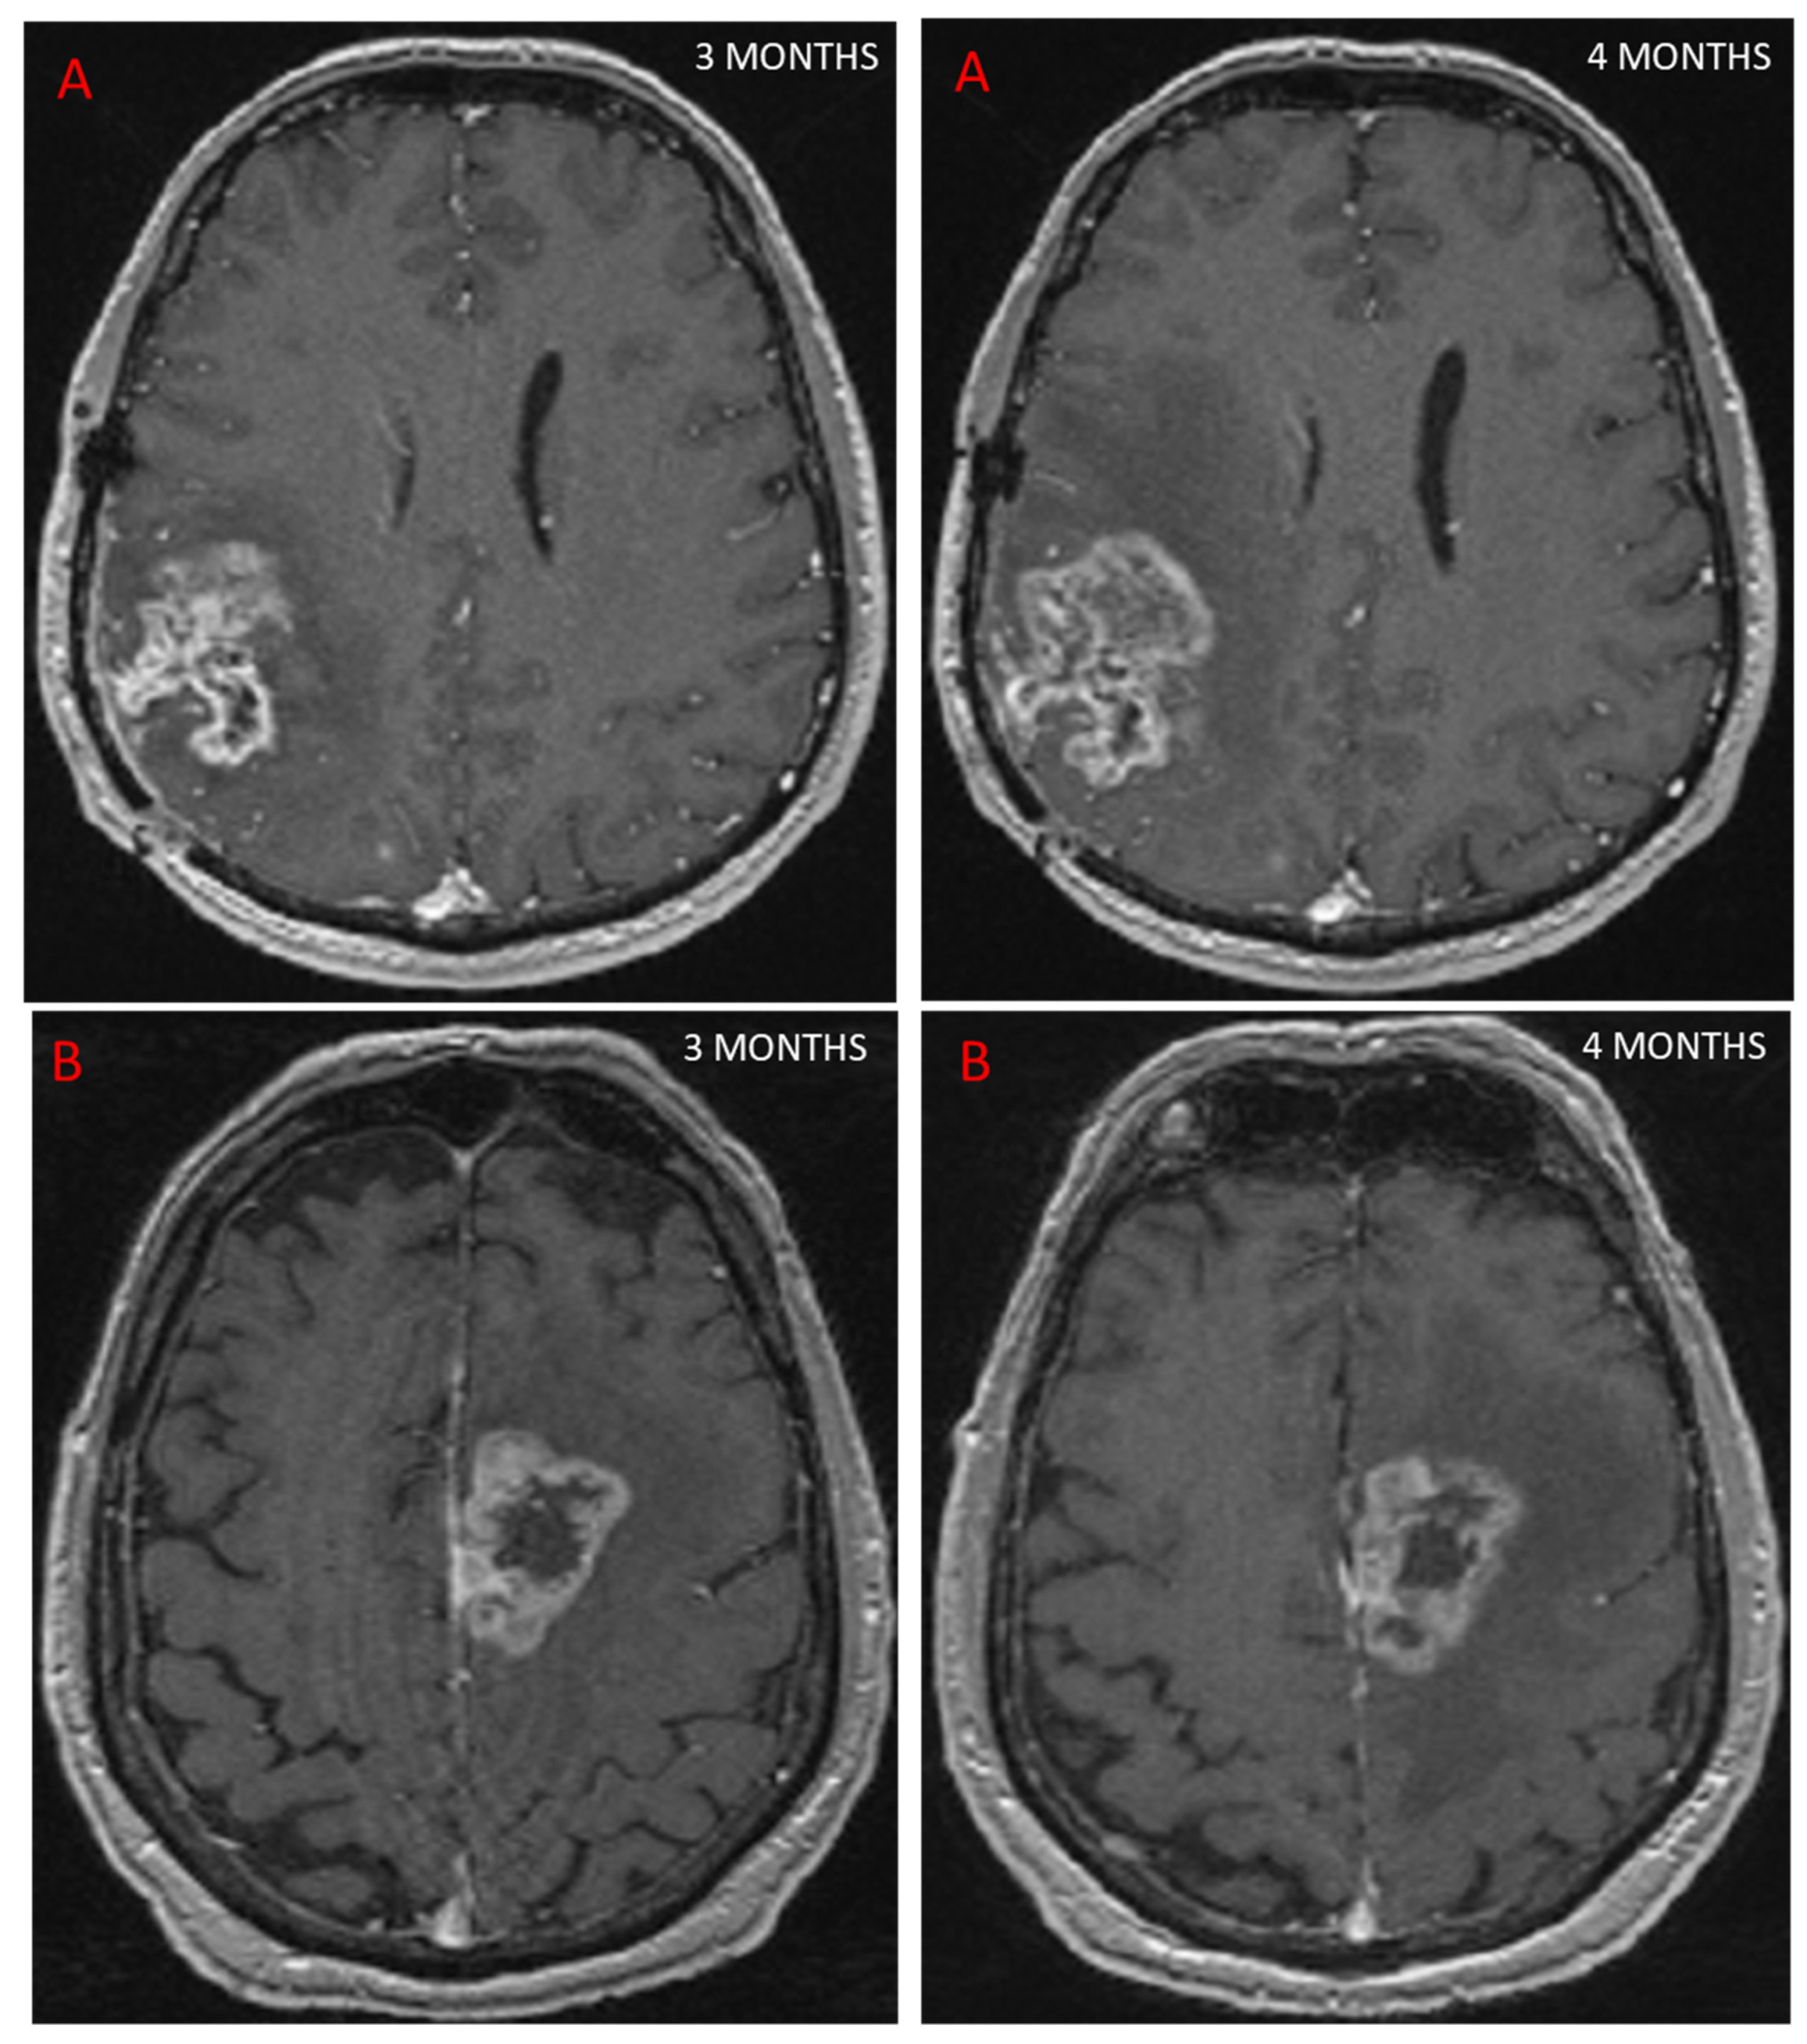

Follow-up MRI assessing GBM response to treatment is useful for depicting PsP, as the contrast enhancement portion of the lesion either remains stable or diminishes over time [24]. However, conventional MRI does not allow a reliable distinction to be made between PsP and TP, as both may be characterized by mass effect, perilesional edema, and contrast agent enhancement due to blood–brain barrier breakdown [25], (Figure 2). In a study of 93 patients [25] looking for different signs on conventional MRI to distinguish between PsP and TP, the only sign for TP was subependymal enhancement, with 38.1% sensitivity, 93.3% specificity, and 41.8% negative predictive value. In a meta-analysis, conventional MRI (166 patients) had a pooled sensitivity and specificity of 68% (95%CI [51, 81]) and 77% (95%CI [45, 93]) [22]. Owing to these limitations, other MRI modalities have been studied to evaluate their ability to diagnose PsP.

Figure 2.

This figure shows two patients treated for GBM with concurrent RT and chemotherapy. At 3 months, MRI showed an increase in contrast-enhancing lesion on axial T1 sequence after injection of a contrast agent, suggestive of progression in both cases. Further MRI scans performed 1 month later (4 months post-RT) showed that one patient had TP, with an increase in contrast (A), while the other patient had PsP, as the contrast remained stable (B).